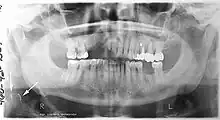

.jpg.webp)

Orthopantomograms (OPTs) are used by health care professionals to provide information on:

- Impacted wisdom teeth diagnosis and treatment planning - the most common use is to determine the status of wisdom teeth and trauma to the jaws.